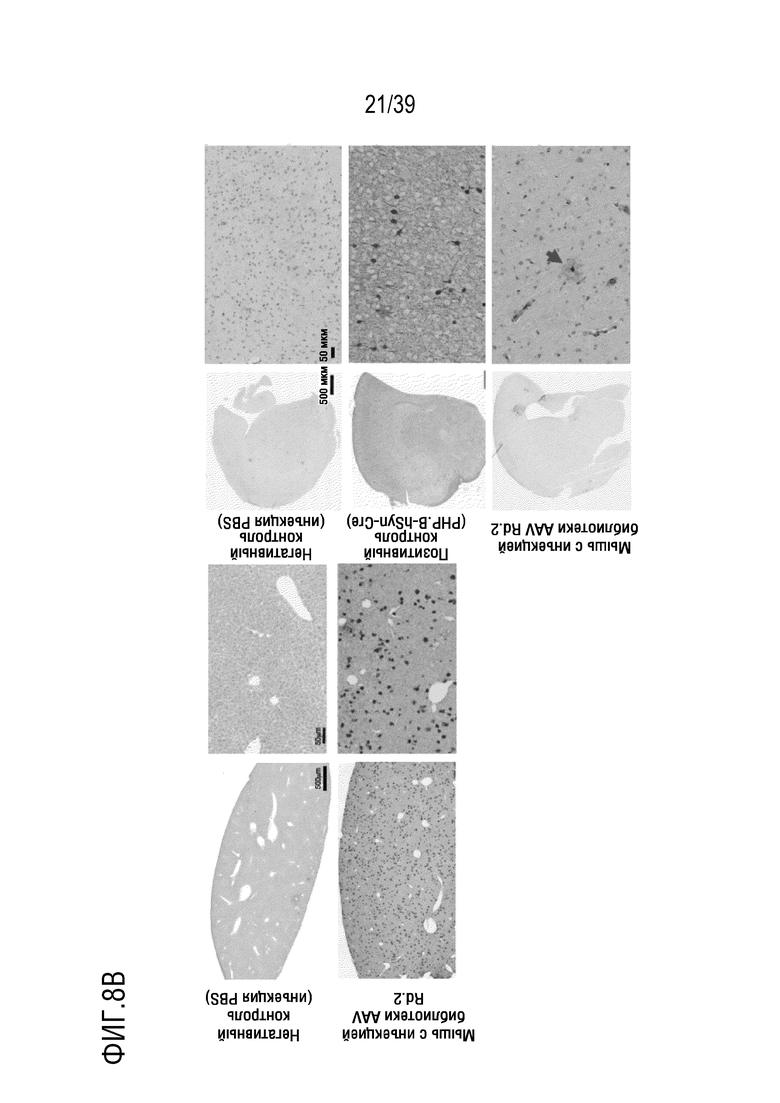

Фиг. 8A-В. Отбор на основе Cre в раунде 2 выявляет компетентные по трансдукции AAV. а. Анализ tdTomato-позитивных клеток методом проточной цитометрии. После разрушения головного мозга мышей, суспензия клеток была проанализирована и отсортирована на наличие tdTomato-позитивных клеток, при этом, стробирование было проведено на основе прямого и бокового рассеяния (FSC, SSC) для исключения нежизнеспособных клеток (общие события) и захвата только отдельных клеток (синглетов), и, наконец, для экспрессии tdTomato (tdTomato+/--клеток). Для отбора tdTomato-позитивных клеток из головного мозга, трансдуцированного библиотекой AAV, стробирование было осуществлено на основе негативного контроля (Ai9 с инъекцией PBS) и позитивного контроля (мышей Ai9, трансдуцированных AAV9-PHP.B, несущей hSyn-Cre-нейрон-специфический кластер). b. Cre-зависимые события рекомбинации были обнаружены после иммунологического окрашивания DAB на tdTomato в печени и в головном мозге после инъекции библиотеки в раунде 2 (по сравнению с инъекциями PBS или AAV9-PHP.B hSyn-Cre). Стрелка указывает на позитивные клетки (астроциты) в головном мозге мышей, которым инъецировали библиотеку AAV.